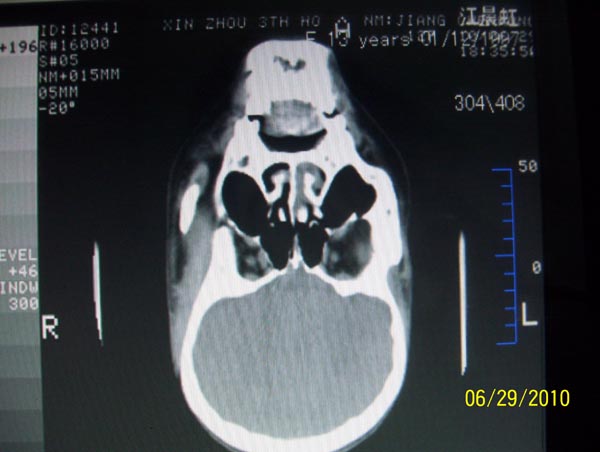

以下是引用随光逐影在2010-6-29 22:28:00的发言:[br]1)右侧下鼻甲肥大(或息肉样变)。2)鼻咽腺样体肥大。

以下是引用拾荒者在2010-6-30 19:22:00的发言:[br]右侧下鼻甲粘膜肥厚,鼻腔阻塞,鼻旁窦窦腔清晰,支持考虑慢性鼻炎。